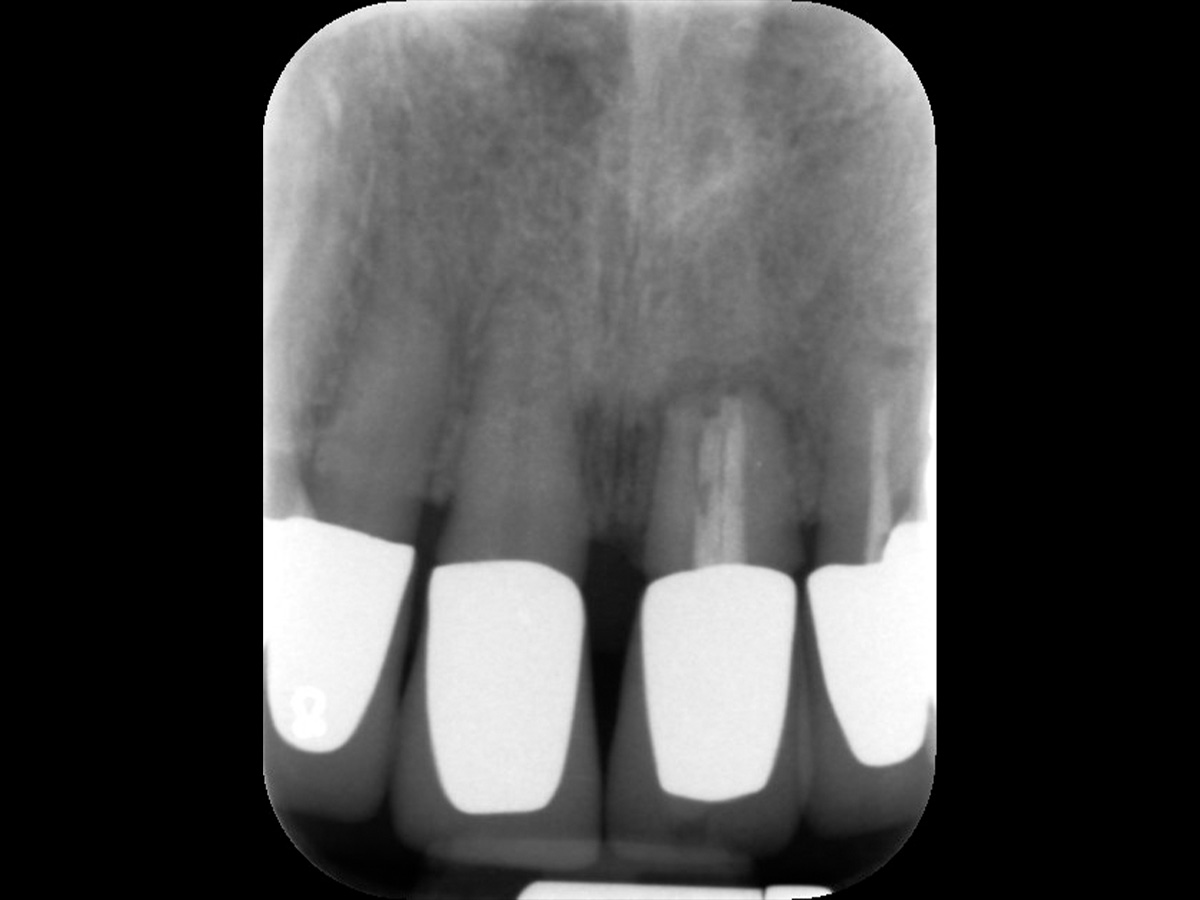

Abbildung 1

Die Röntgenaufnahme zeigt, dass Zahn 21 nicht zu erhalten ist.